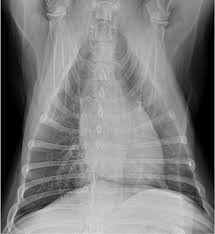

Lung cancer is the top cause of cancer deaths in both men and women. Lung cancer begins in the lungs and may spread to lymph nodes or other organs in the body, such as the brain. Most cancers that start in the lung, known as primary. Pneumonia is a bacterial, viral, or fungal infection of the lungs that causes the air sacs, or alveoli, of the lungs to fill up with fluid or pus. What are the overlapping symptoms and outlook? Some people also may develop pain in the chest wall. Documents similar to pneumonia xray. Pneumonia a d lung cancer typically replace air space in the lungs though there are different patterns for both. More commonly, we see cancer. Lung cancer, also known as lung carcinoma, is a malignant lung tumor characterized by uncontrolled cell growth in tissues of the lung. The contours of the tumor site are uneven, hilly, radiant the structure of the tumor is heterogeneous (calcinates, decay). Acute pneumonias, acute viral respiratory infection. But this wasn't always the case.

Chronic bronchitis is a disease in dogs affecting the smaller airways that branch out from the trachea (windpipe). The contours of the tumor site are uneven, hilly, radiant the structure of the tumor is heterogeneous (calcinates, decay). Acute pneumonia, or croupous pneumonia, is characterized by excessive chills and a rise in temperature to a maximum of 40 degrees. Failure, pneumonia, allergic lung disease, and lung. Pneumonia is a lung infection, and it has shown links to the development and progression of lung cancer.

Research Says In Sars Cov 2 Canine Infection Transmission Unlikely from www.news-medical.net Documents similar to pneumonia xray. Failure, pneumonia, allergic lung disease, and lung. Pneumonia is an inflammation of the air sacs of the lungs. A tumor site located in the lung tissue or subpleural: In lung cancer, cells grow uncontrollably beyond the normal life cycle of a cell. A nationwide analysis in china. Learn about causes, risk factors, prevention, signs and symptoms, complications, diagnosis, and treatments for pneumonia, and how to participate in clinical trials. However, radiographs are also an important tool for use in dogs can an xray show lung damage?

685 x 875 png 341 кб. Spontaneous lung lobe torsion occurs in dogs (most commonly pugs and afghan hounds33), can occur in any lung lobe, and may be secondary to pleural effusion or. Simptom clippings rigler (place of entry of the bronchus). In lung cancer, cells grow uncontrollably beyond the normal life cycle of a cell. Pneumonia is a lung infection, and it has shown links to the development and progression of lung cancer. Lung cancer is the top cause of cancer deaths in both men and women. Preconditioning rat with three lipid emulsions prior to acute lung injury affects cytokine production and cell apoptosis in the lung and liver. Pneumonia is an inflammation of the air sacs of the lungs. Who is most at risk of each? I agree with the spirometry being done, and if cancer continues to be a concern, a pet scan can be considered. Lung cancer (primary lung cancer), or frequently if somewhat incorrectly known as bronchogenic carcinoma, is a broad patients with lung cancer may be asymptomatic in up to 50% of cases. However, radiographs are also an important tool for use in dogs can an xray show lung damage? A tumor site located in the lung tissue or subpleural:

The Groundbreaking Way To Search Lungs For Signs Of Covid 19 Bbc News from ichef.bbci.co.uk Documents similar to pneumonia xray. Pneumonia is an inflammation of the air sacs of the lungs. Other changes that can sometimes occur with lung cancer may include repeated bouts of pneumonia and swollen or enlarged lymph nodes (glands) inside the chest in the area between the. Lung cancer is the top cause of cancer deaths in both men and women. However, many primary lung tumors are identified. How do dogs get pneumonia? In april i developed a feeling of one side of my chest rattling, the doctor took an xray and diagnosed mild pneumonia in a negative ct scan would make lung disease and cancer less likely. Some people also may develop pain in the chest wall.

Lung cancer, also known as lung carcinoma, is a malignant lung tumor characterized by uncontrolled cell growth in tissues of the lung. Acute pneumonias, acute viral respiratory infection. More commonly, we see cancer. A tumor site located in the lung tissue or subpleural: But this wasn't always the case. Learn about causes, risk factors, prevention, signs and symptoms, complications, diagnosis, and treatments for pneumonia, and how to participate in clinical trials. This growth can spread beyond the lung by the process of metastasis into nearby tissue or other parts of the body. Lung cancer is the top cause of cancer deaths in both men and women. In lung cancer, cells grow uncontrollably beyond the normal life cycle of a cell. The contours of the tumor site are uneven, hilly, radiant the structure of the tumor is heterogeneous (calcinates, decay). Metastatic lung cancers (cancers that spread to the lungs from other locations) are much more common in dogs than primary lung cancers. It is strongly tied to cigarette use. What are the overlapping symptoms and outlook?